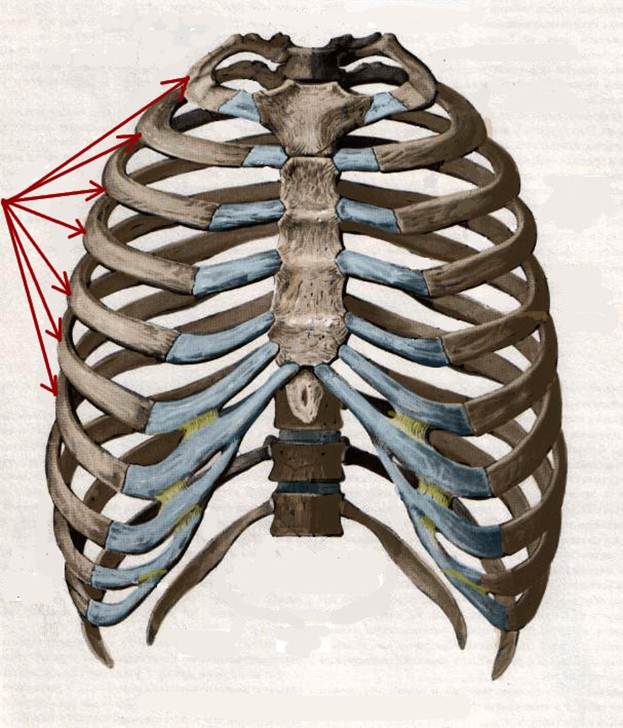

S: Стрелки указывают на сostae verae (латинский язык).